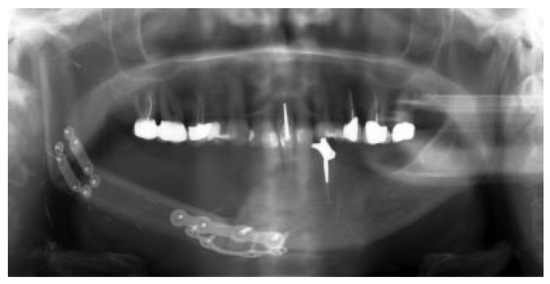

In 15 patients, 14 ablative surgical interventions were recorded, with 14 receiving primary or secondary reconstructive procedures; in one patient, no reconstructive procedure was performed due to a compounding medical condition (Table 2). This patient was excluded from further analysis due to lack of reconstruction. Eight patients had primary head and neck cancer, but in only four patients the condyle was involved due to infiltration, while four suffered from ORN. One patient suffered from a rare benign tenosynovial giant cell tumor. Two patients suffered from extensive osteomyelitis, and bisphosphonate osteonecrosis afflicted two patients. One patient had to be operated on twice due to hypertrophic bone formation around the metal condylar head and represents the only major complication in our series. She suffered facial nerve damage during the second surgery in a postradiated field, with the facial nerve lying on the reconstruction plate used in the first surgery (Figure 1). Six of the fourteen reconstruction surgeries took place in a radiated field, explaining the two plate exposures in an unrelated area, away from the condylar reconstruction. Two patients received total joint reconstructions combined with one and in the other two free flaps. Five patients received fibula flaps alone and one received a vascularized costochondral graft, while all of the others had metal condylar prostheses with or without a free flap (Figure 2, Figure 3 and Figure 4). Follow-up ranged from 2 to 84 months with an average of 30 months. In total, five patients suffered from complications that could be considered acceptable, as they all could be corrected with minor revision surgery or occlusal adjustment. One patient suffered from facial nerve damage after a reconstruction plate in which metal condyle had to be removed in a radiate. In 11 patients, reliable information was obtained regarding mouth opening of which 9 showed a marked improvement of more than 5 mm. Three patients had a decrease in mouth opening, but all could be regarded as functional as no mouth opening of less than 30 mm was recorded (Figure 4).

Figure 3.

Composite fibula free vascularized flap in place.